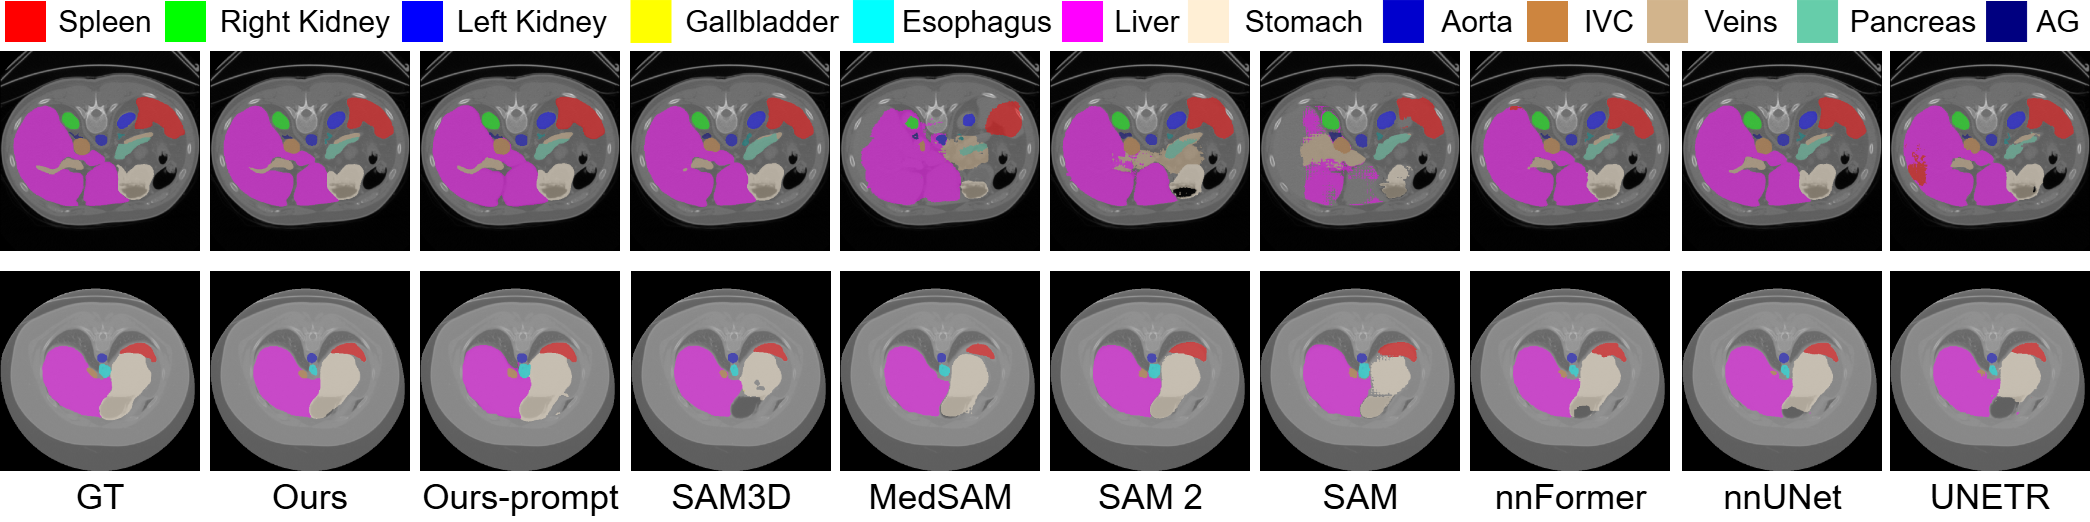

Refer to caption

Figure 4: Qualitative comparison on BTCV dataset. RFMedSAM 2 is the most precise for each class and has fewer segmentation outliers.

4.2 Comparison with State-of-the-Art Methods

4.2.1 Results on the AMOS22 Dataset.

Table 2 presents the quantitative results on the AMOS22 dataset, comparing our proposed RFMedSAM 2 with widely recognized segmentation methods, including CNN-based methods (nnUNet [11]), transformer-based methods (UNETR [9], SwinUNETR [8], nnFormer [28]), and SAM-based methods (SAM [13], SAM 2 [19], MedSAM [16], SAMed [26], and SAM3D [2]). To ensure fairness, all methods are evaluated using 5-fold cross-validation without ensemble techniques.

We observe that our RFMedSAM 2 outperforms all existing methods on most organs, achieving a new state-of-the-art performance in DSC. When utilizing the predictions from nnUNet for bounding box prompts, SAM, SAM 2, and MedSAM exhibit decreases of 34%, 18%, and 27%, respectively, compared to nnUNet’s accuracy of 87.8%. These reductions in accuracy indicate negative implications for the results. SAM 2 achieves the best performance, which demonstrates it presents the strongest zero-shot capabilities. Specifically, RFMedSAM 2 surpasses nnUNet by 2.9% in DSC, respectively. RFMedSAM 2 surpasses SAMed and SAM3D by 23% and 25% in DSC, respectively. The significant improvement demonstrates our proposed prompt-free RFMedSAM 2 is better than other prompt-free SAM models. In the extremely hard AMOS 2022 dataset, our RFMedSAM 2 achieves state-of-the-art performance, which confirms the efficacy of our method.

4.2.2 Results on the BTCV Dataset.

Table 3 shows the quantitative performance on the BTCV dataset, comparing RFMedSAM 2 with leading SAM-based methods with proper prompts(i.e., SAM [13], SAM2 [19], MedSAM [16], SAM-U [6], and SAM-Med2D [5]), SAM-based methods without prompts (i.e., SAMed [26] and SAM3D [1]), convolution-based methods (VNet [20] and nnUNet [11]), transformer-based methods (TransUNet [4], SwinUNet [3], and nnFormer [28]). We observe that RFMedSAM 2 outperforms all existing methods, setting a new state-of-the-art benchmark. When provided with proper prompts, RFMedSAM 2 achieves a DSC of 92.3%, representing a significant 5% improvement over the previous state-of-the-art method. In comparison, among SAM-based methods with the proper prompts, the best performance, achieved by SAM-Med2D, reaches only 84.7%. Our proposed RFMedSAM 2 surpasses this by 7.6%, highlighting its superior effectiveness over SAM-based methods with prompts. When prompts are not provided, our proposed prompt-free RFMedSAM 2 outperforms the other prompt-free SAMed and SAM3D by 9% and 6%, respectively. Compared with non-SAM-based methods, our method surpasses nnUNet and nnFormer by 6.4% and 1% in DSC for the highly saturated dataset. In Figure 4, we illustrate qualitative results compared to representative methods. These results also demonstrate that our RFMedSAM 2 can predict more accurately the ‘Stomach’, ‘Spleen’, and ‘Liver’ labels.